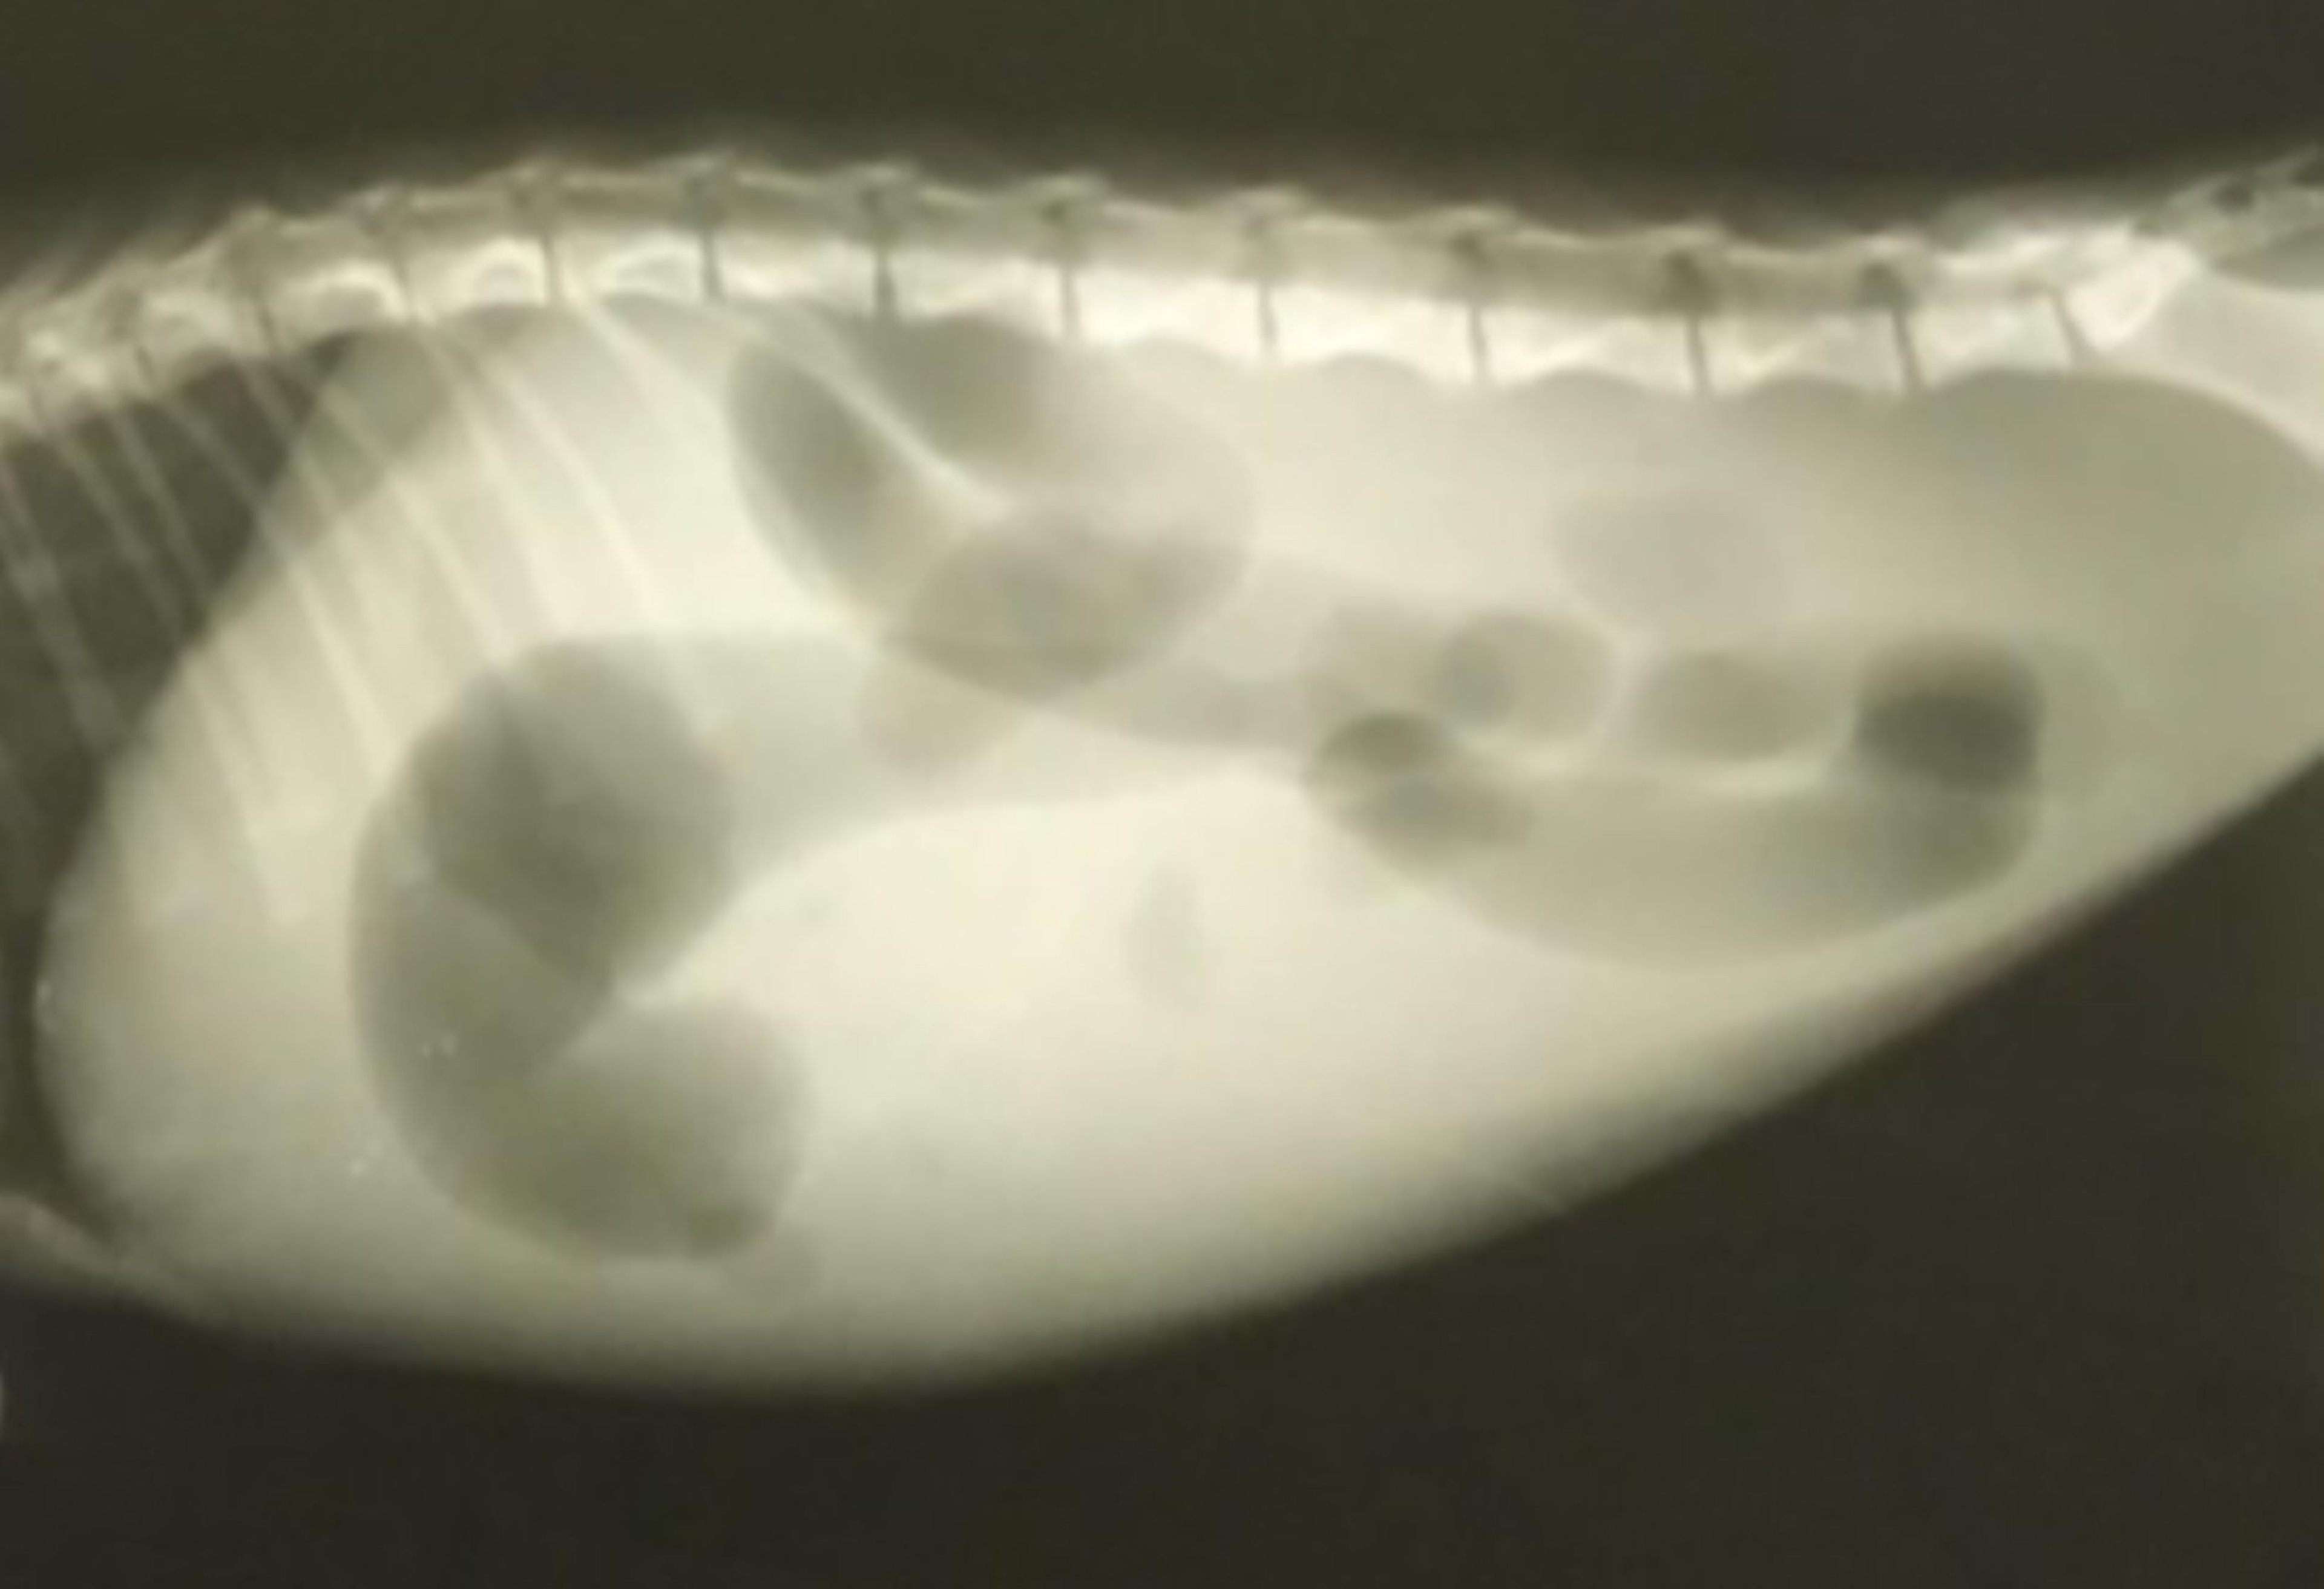

Peritonitis infecciosa felina, ascitis, radiografía

Proyección radiográfica abdominal lateral derecha de un gato macho doméstico de pelo corto castrado de 3 años con derrame peritoneal debido a peritonitis infecciosa felina. Cabe observar la mayor opacidad difusa del tejido blando y la pérdida de detalle seroso.